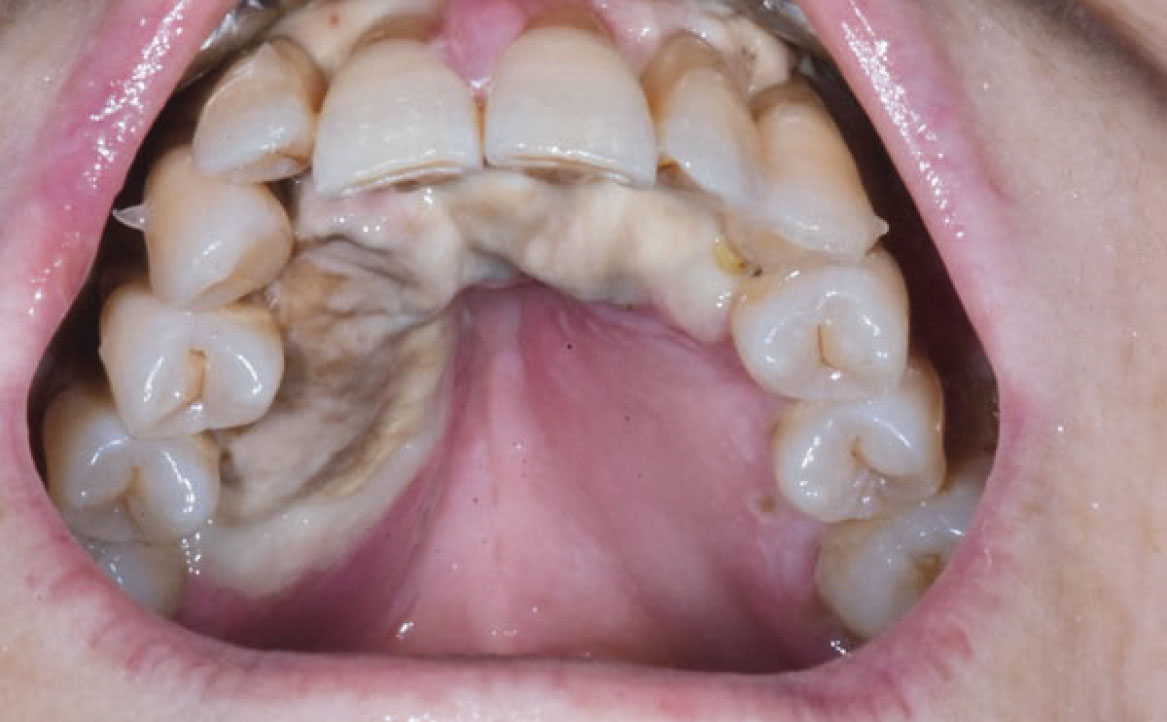

Le patologie vescicole-bollose rappresentano un gruppo di condizioni caratterizzate dalla formazione di vescicole e bolle sulla mucosa orale e sulla cute. Tra queste, il pemfigo volgare è una patologia cronica di natura autoimmune che coinvolge frequentemente la mucosa orale. Le lesioni bollose del pemfigo volgare hanno la tendenza a rompersi facilmente, causando ulcere dolorose. Alcuni farmaci possono indurre lesioni orali clinicamente e istologicamente simili al pemfigo, producendo autoanticorpi diretti contro le molecole desmosomiali e causando acantolisi cheratinocitaria (21). Tra i farmaci più associati a questa condizione vi sono la penicillamina, la rifampicina, il diclofenac e alcuni ACE-inibitori. Inoltre, anche i FANS come il diclofenac, l’ibuprofene e il piroxicam, il fenobarbital, la fenilbutazone, il propranololo e l’eroina possono provocare lesioni simili al pemfigo (fig. 5) (22).

Il pemfigoide delle membrane mucose è un’altra malattia vescicolo-bollosa cronica, caratterizzata dal deposito di IgG, IgA o C3 lungo la membrana basale dell’epitelio. Sebbene simile al pemfigo nel meccanismo patogenetico, il pemfigoide coinvolge gli emi-desmosomi, causando la formazione di bolle sotto-epiteliali. Questa condizione si manifesta con lesioni bollose che interessano principalmente la mucosa orale, la congiuntiva oculare, la mucosa nasale, l’area anogenitale, faringe, laringe ed esofago. Il pemfigoide farmaco-indotto colpisce solitamente individui più giovani rispetto al pemfigoide idiopatico (22). I farmaci comunemente associati a questa forma di pemfigoide includono quelli contenenti componenti tiolici e sulfamidici, oltre ad antiaritmici, antipertensivi, antidiabetici, diuretici, antibiotici, agenti antireumatici, anti-TNF α, antipsicotici e FANS (fig. 6) (23).